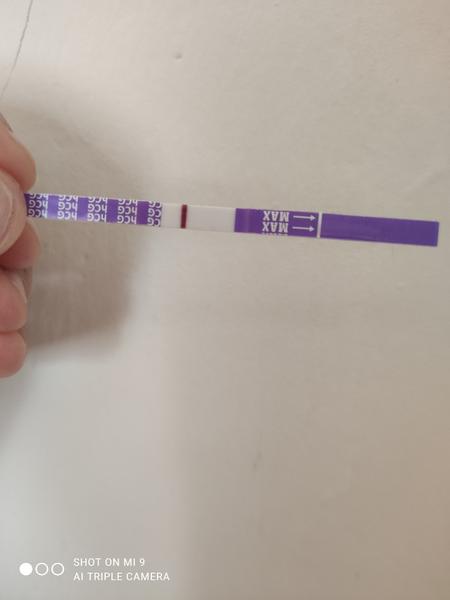

Je to duch či ryska?

Ahoj je to duch či ryska? Skúšala som to dať i do negatívu. Mám 10 dní od styku.

Za mna negat.

Tak ja patrím k tým čo má asi dobré oči 🤣 na každej fotke vidím samozrejme slabulinko ale niečo tam je ak to je do ružová tak sa ale neteš moc ešte stále nemáš nič vyhráte .o 2 dní testuje verím že tie čo nevidia už uvidia

Treba skúsiť iný test pozajtra ráno. Toto je Mamatest a keby tam aj bola naznačená čiarka, pravdepodobne iba falošne pozitívna.

Nie je tam ani duch ani kanalik